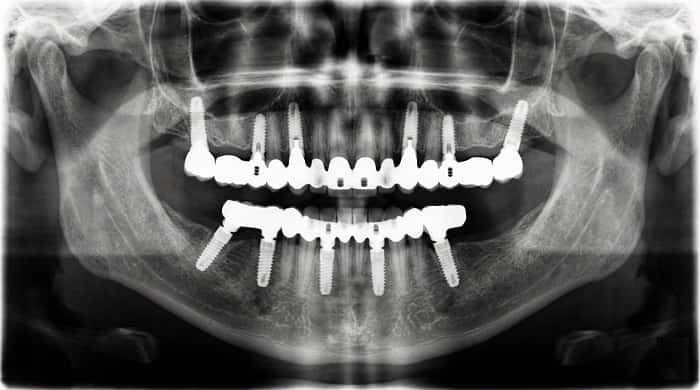

انواع پروتز ثابت روی ایمپلنت زمانی که یک یا چند دندان از دست میرود، ایمپلنت دندانی این امکان را میدهد که جایگزینی نزدیک به دندان طبیعی ایجاد شود. اما آنچه بیمار در نهایت میبیند و با آن میجوَد، پروتز ثابت روی ایمپلنت است؛ یعنی روکش یا پروتزی که روی ایمپلنت سوار میشود و شکل و عملکرد دندان را بازسازی میکند. شناخت انواع پروتز ثابت روی ایمپلنت به دندانپزشک کمک میکند برای هر بیمار، گزینهای متناسب با شرایط استخوانی، نیاز زیبایی و الگوی فانکشن انتخاب کند.

پروتز فول آرچ ثابت روی ایمپلنت

در بیماران بیدندان، پروتز کامل فک بالا یا پایین میتواند بهصورت فول آرچ ثابت روی چند ایمپلنت اجرا شود. این نوع پروتز، جایگزین دست دندان متحرک است و از نظر فانکشن و ثبات، تجربه کاملاً متفاوتی برای بیمار فراهم میکند. ساختار فول آرچ ممکن است هیبرید فلز–آکریل، زیرکونیا یا ترکیبی از متریالها باشد. توضیحات تکمیلی در مقاله فول آرچ روی ایمپلنت بهصورت اختصاصی ارائه شده است.

- تعداد و موقعیت ایمپلنتها و کیفیت استخوان.

- الگوی نیرو و وجود براکسیسم یا پارافانکشن.

طول عمر پروتز ثابت روی ایمپلنت چقدر است؟

طول عمر به عوامل متعددی مانند کیفیت طرح درمان، نوع پروتز، متریال، رعایت بهداشت دهان، کنترل پارافانکشنها و مراجعات دورهای بستگی دارد. اگر این موارد بهدرستی مدیریت شوند، ایمپلنت و پروتز ثابت میتوانند سالها عملکرد پایدار داشته باشند و در صورت نیاز، اجزای ترمیمی قابل تعمیر یا تعویض هستند.